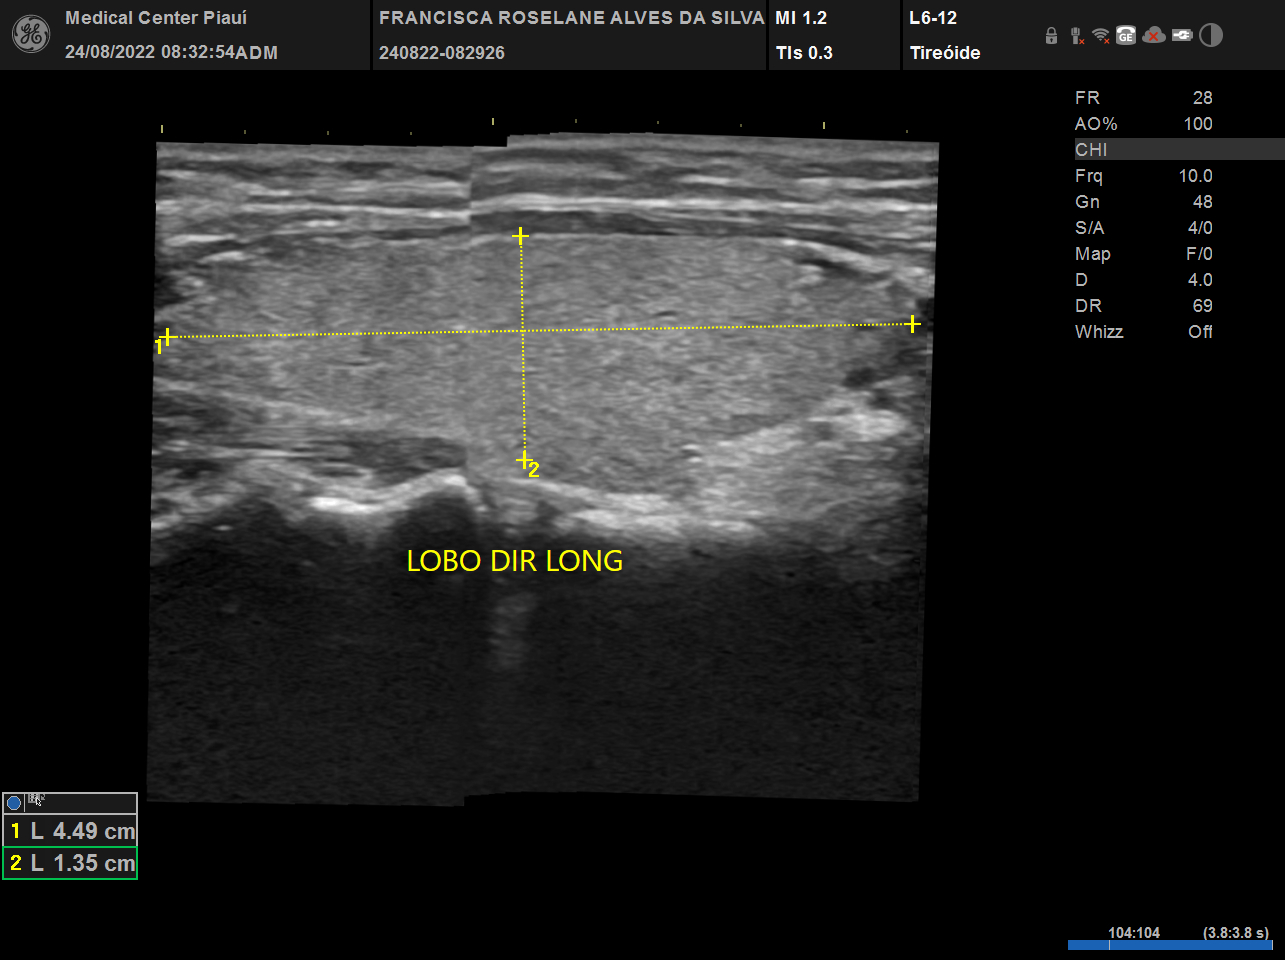

USG, TC e RN de tireoide